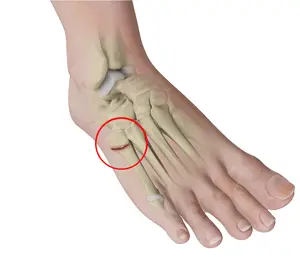

fracture

a break in a bone

types of fractures

open (compound) fracture, closed (simple) fracture, comminuted fracture, greenstick fracture, impacted fracture, and stress fracture

stress fracture

microscopic fissures in bone but no visible break due to repeated, strenuous activities such as running, jumping , or aerobic activities